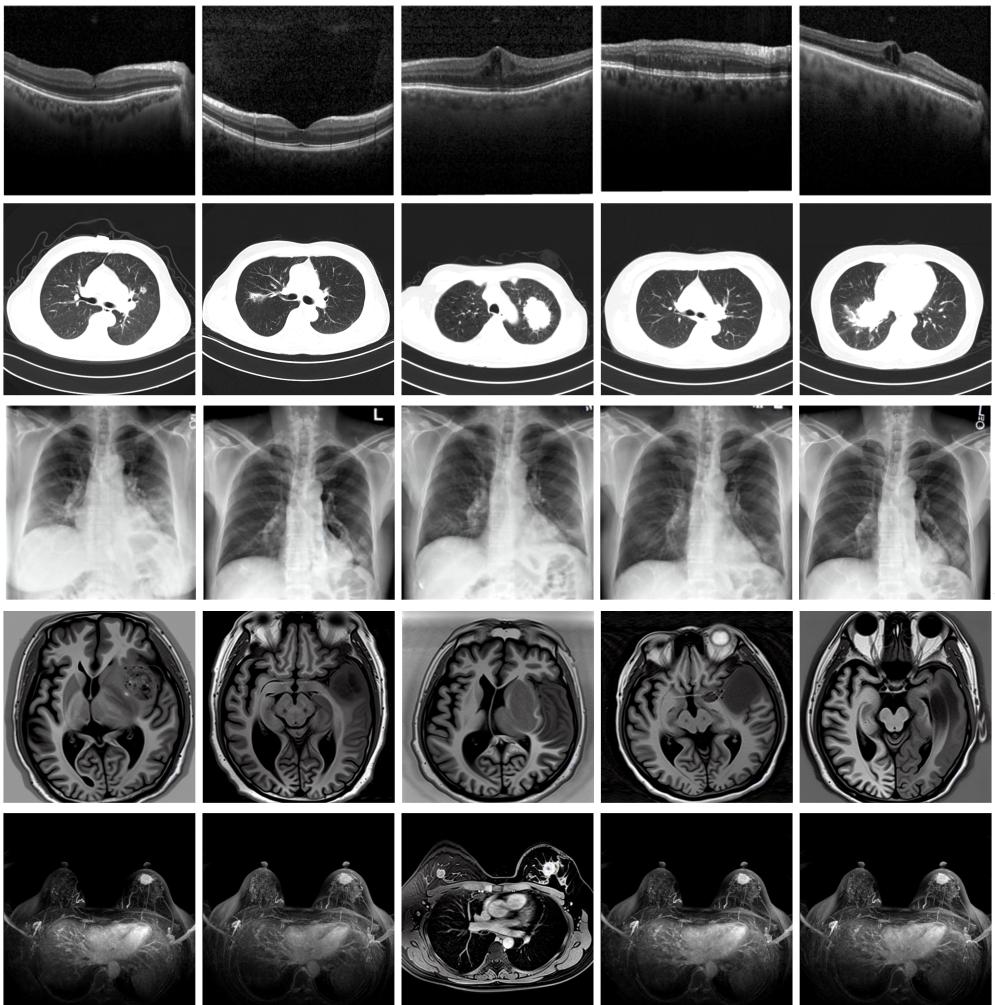

圖為由MINIM生成的高質(zhì)量醫(yī)學(xué)合成圖像(受訪者供圖)

“目前公開(kāi)的醫(yī)學(xué)影像數(shù)據(jù)非常有限,我們建立的生成式模型有望解決訓(xùn)練數(shù)據(jù)不夠的問(wèn)題。”北京大學(xué)未來(lái)技術(shù)學(xué)院助理研究員王勁卓說(shuō),研究團(tuán)隊(duì)利用多種器官在CT、X光、磁共振等不同成像方式下的高質(zhì)量影像文本配對(duì)數(shù)據(jù)進(jìn)行訓(xùn)練,最終生成海量的醫(yī)學(xué)合成影像,其在圖像特征、細(xì)節(jié)呈現(xiàn)等多方面都與真實(shí)醫(yī)學(xué)圖像高度一致。

實(shí)驗(yàn)結(jié)果顯示,MINIM生成的合成數(shù)據(jù)在醫(yī)生主觀評(píng)測(cè)指標(biāo)和多項(xiàng)客觀檢驗(yàn)標(biāo)準(zhǔn)方面達(dá)國(guó)際領(lǐng)先水平,在臨床應(yīng)用中具有重要參考價(jià)值。在真實(shí)數(shù)據(jù)基礎(chǔ)上,使用20倍合成數(shù)據(jù)在眼科、胸科、腦科和乳腺科的多個(gè)醫(yī)學(xué)任務(wù)準(zhǔn)確率平均可提升12%至17%。